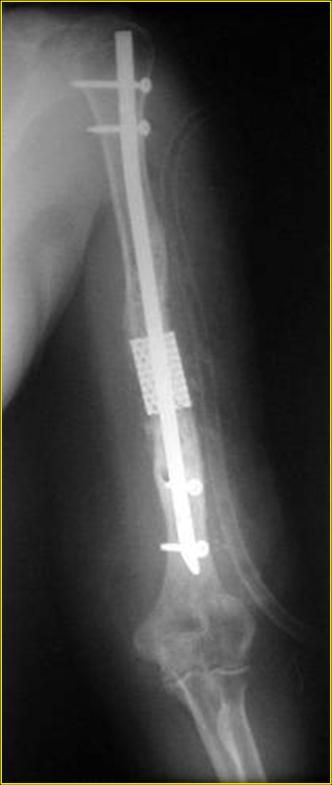

Типичная положительная ситуация для интрамедуллярного остеосинтеза с

использованием опорного металлокаркаса для компенсации дефекта.

Рентгеновская версия реконструкции. хронология:

после операции, 2 мес. после операции, через 1 год

Движения в полном объеме восстановлены к 2 мес. после операции. Если надо могу показать мультик. Сейчас уже прошло более 3 лет, больная не

показывается. Успехов ЛАФ.